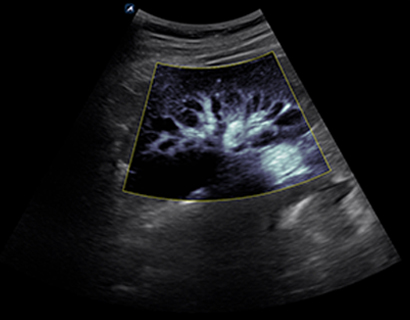

SC2-11H

X+ Crystal Signature™ Microconvex(2~11MHz)

Application:

Abdomen, Pediatric, OB/GYN, Urology, EM